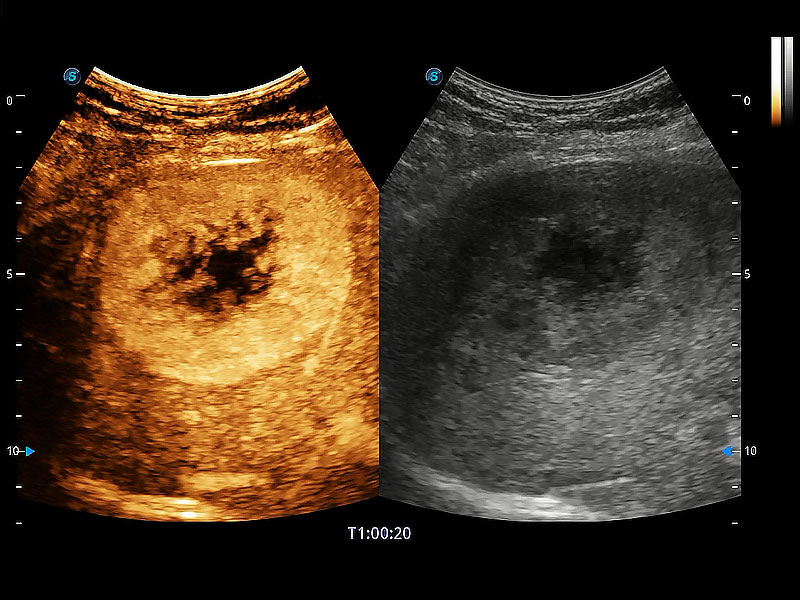

(犬)肝脏

(猫)胆囊